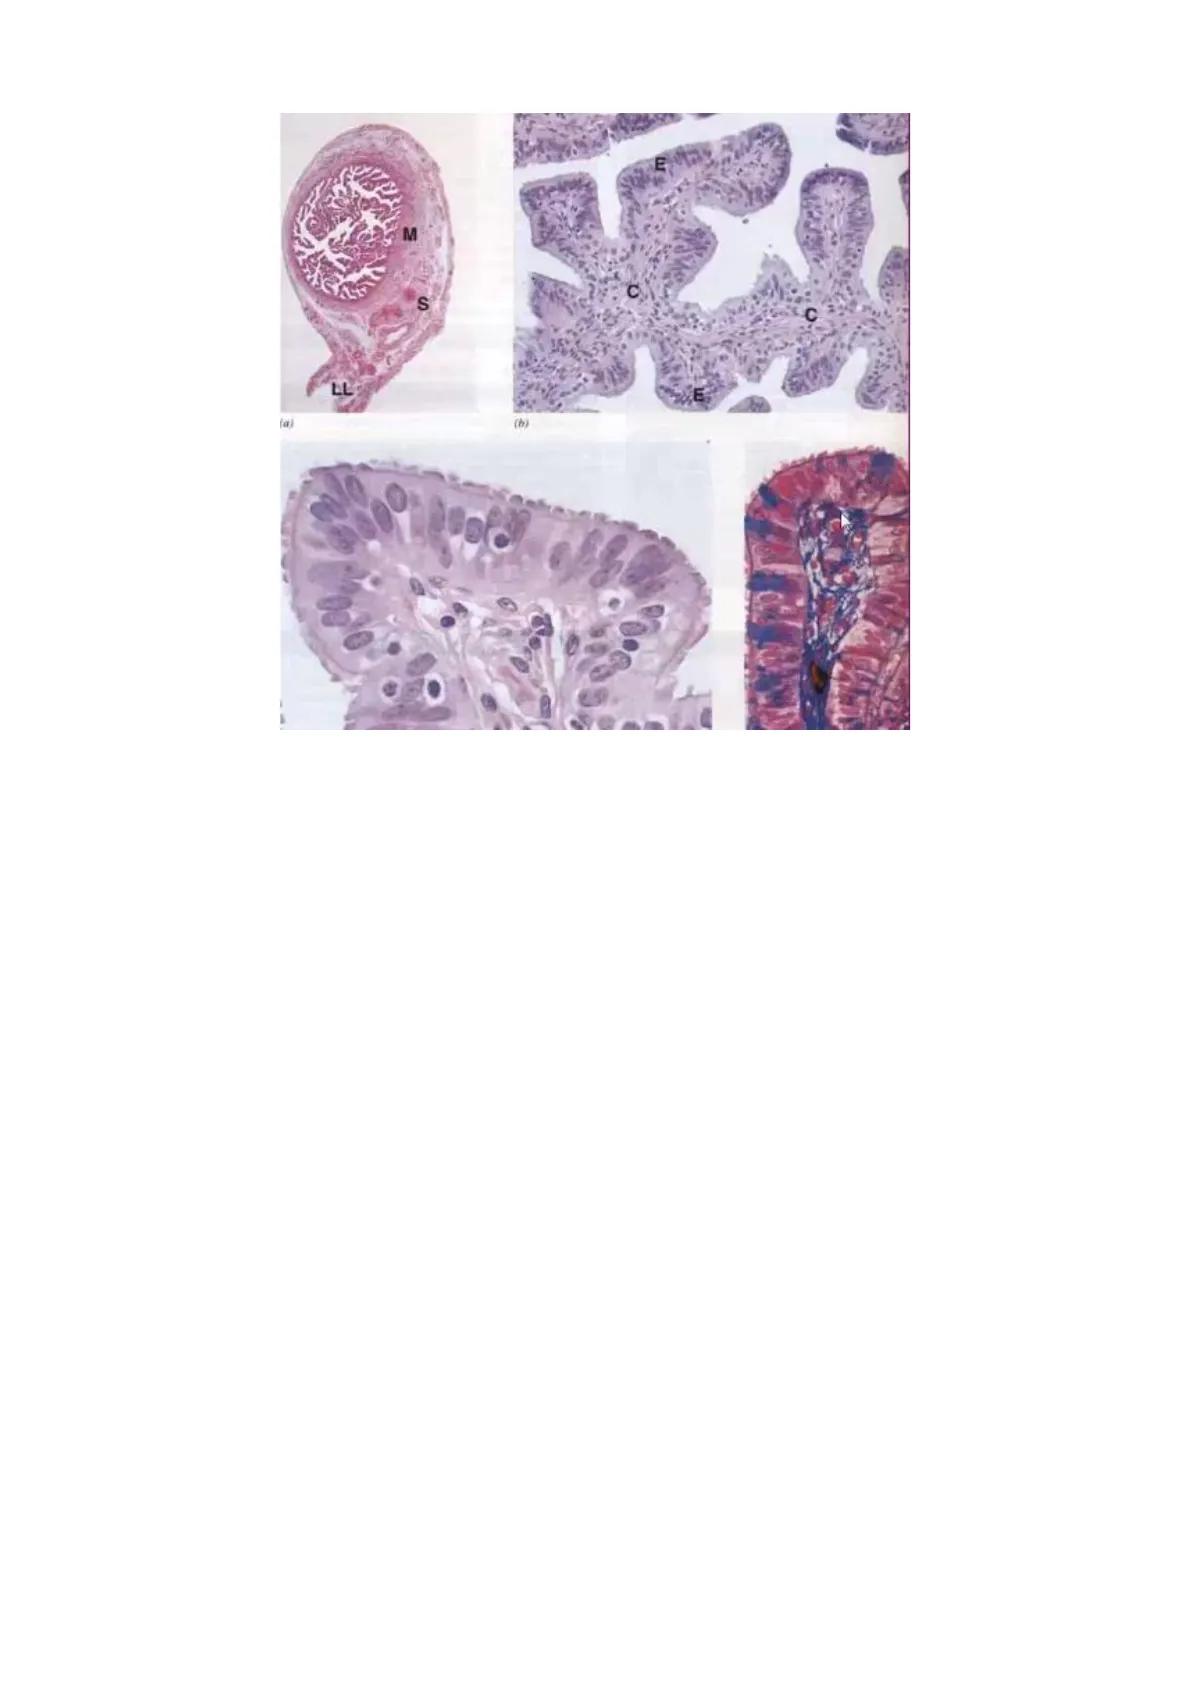

Il collo dell'utero ha una forma cilindroide o fusiforme (è slargato nel suo tratto centrale). Ha una lunghezza di 2-3 cm e su di esso si inseriscono le pareti della vagina. Sul collo dell'utero distinguiamo una faccia anteriore, una faccia posteriore e 2 margini laterali. Proprio per l'inserzione delle pareti della vagina sul collo dell'utero, questo è suddiviso in 2 porzioni:

L'orifizio uterino esterno ha una diversa morfologia